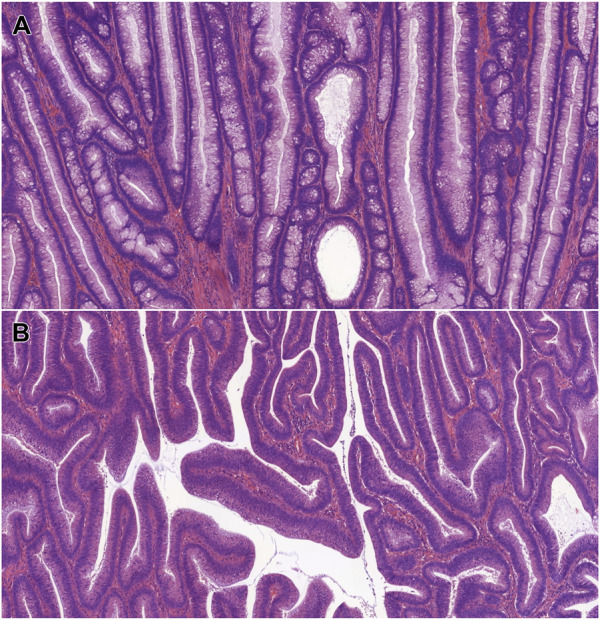

Abstract Image